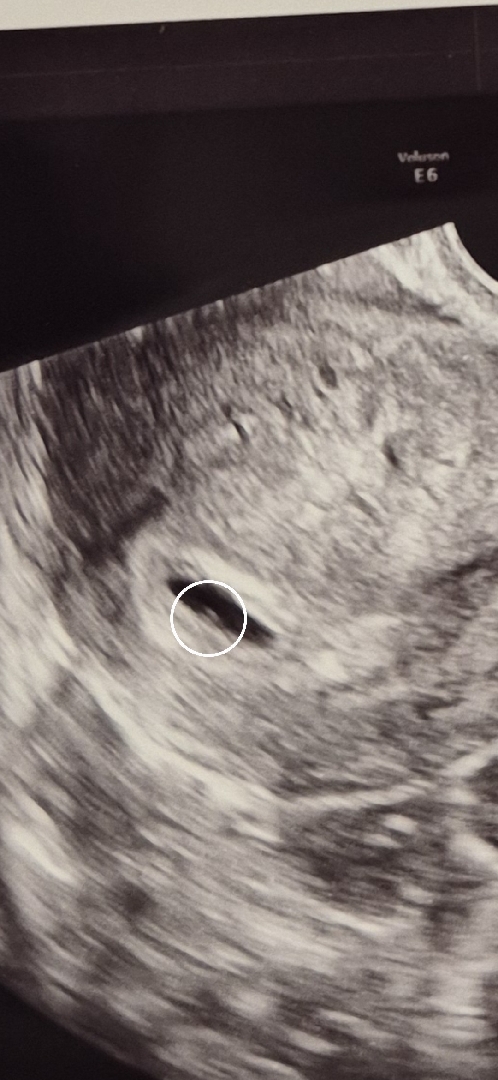

5주 이게 난황일까요?ㅠㅠ

너무 작기도하고 뭐가뭔지 잘 모르겠어요😭😭

난황맞는거같아요! 저도 5주차에 사진 비슷했어요~~